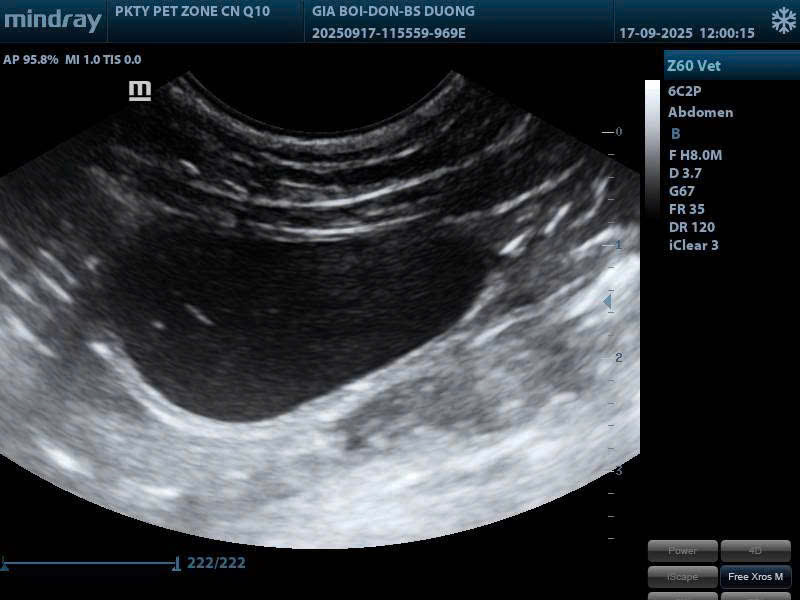

Siêu âm là phương thức lý tưởng để khảo sát mô mềm và cho phép quan sát các cấu trúc chuyển động trong thời gian thực.

Siêu âm được xem là một trong những phương pháp được sử dụng nhiều nhất trong thực hành thú y nhờ độ an toàn tuyệt đối và khả năng đánh giá theo thời gian thực. Không dùng tia xạ, không gây tổn thương, siêu âm phù hợp với mọi đối tượng: chó mèo con, thú già yếu, vật mang thai và cả những ca bệnh cần theo dõi nhiều lần.

Siêu âm là phương thức đánh giá đặc biệt hiệu quả trong khảo sát ổ bụng, hệ sinh dục, hệ tiết niệu và tim mạch:

- Hình ảnh trực tiếp, sống động: quan sát được co bóp tim, nhu động ruột, dòng chảy mạch máu…

- Phát hiện sớm bất thường: khối u nhỏ, dịch tự do ổ bụng, viêm tử cung, sỏi thận – sỏi bàng quang…

- Theo dõi thai chính xác: xác định tuổi thai, nhịp tim thai và các bất thường thai kì…

- Hỗ trợ thủ thuật: dẫn đường an toàn cho sinh thiết, chọc hút dịch…

Với ưu điểm không xâm lấn, nhanh chóng và an toàn, siêu âm trở thành kỹ thuật lựa chọn đầu tiên trong nhiều tình huống lâm sàng, đặc biệt khi cần theo dõi các quá trình động hoặc bệnh lý cấp tính.